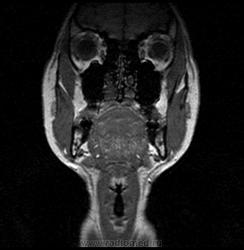

06.06.2011 МРТ - головы и шеи.

Пацентка 36 лет, с жалобами на припухлось в околоушной области справа.

В глубокой доле  правой околоушной железы  на фоне неизмененной паренхимы зона  гетерогенного по Т2, гипоинтенсивного по Т1  с единичными гиперинтенсивными включениями.При контрастировании- накопление контраста диффузное неоднородное и по периферии.Рискну предположить злокачественное образование ( аденокарцинома) с низкой степенью злокачественности( есть капсула, экспансивный рост).Сильно не расстреливайте.

Проблема в том, что перед челюстно-лицевым хирургом стоит распространенность любого объемного процесса, в данном случае все упирается в возмможную травму лицевого нерва и конечно же с дальнейшим его парезом, а ведь женщина  еще молодая. Образование имеет тонкостенную оболочку, по структуре неоднородно, с наличием кальцината, при этом МР-сигнал от окружающих анатомических структур(как костных так и мышечных) не изменен, т.е. об инфильтративном росте речи не идет, в какой то степени доброкачественное. В конкретном случае лицевой нерв с ретромандибулярной веной просто несколько оттеснен.

По гистологии аденома околоушной слюнной железы, но после удаления пока сохраняется парез лицевой мускулатуры, возможно временный.